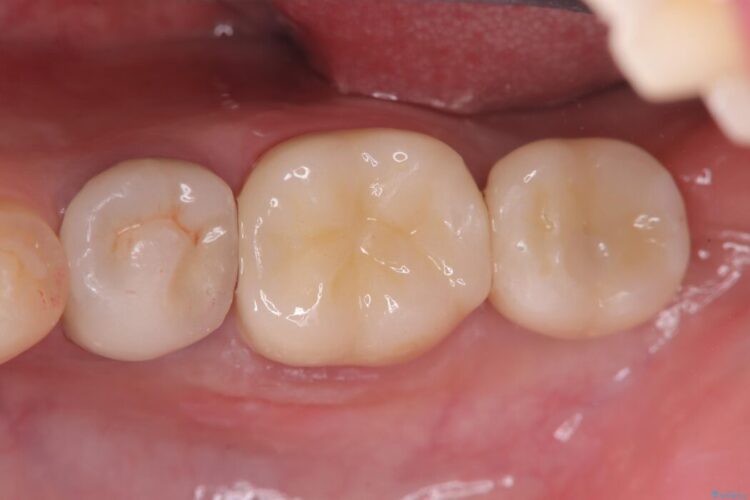

自然な見た目のセラミックインレーで精密に修復

自然な見た目のセラミックインレーで精密に修復 ビフォー 自然な見た目のセラミックインレーで精密に修復 アフター

右上5番に小さな穴があるとご相談にいらした患者様です。